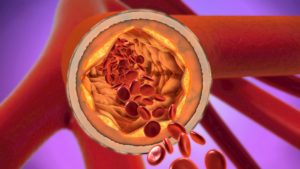

For example, you can’t really tell that blood has an increasingly difficult time moving through your arteries. Over time, your arteries and blood vessels harden and your body doesn’t produce the same chemicals to help promote blood flow. Factor in the potential of atherosclerosis and you could be at major risk for a heart attack or stroke without even knowing it. No wonder heart disease is called “the silent killer.”

Even though you can’t see your arteries hardening, shrinking, or see how well blood is moving, you can take steps to provide some comfort. By eating certain foods, avoiding others, and increasing activity, you’ll have the potential to restore your arteries and reduce the risk for a heart attack.

Another way to improve blood flow is eating more healthy fats. Healthy fats like omega-3’s, polyunsaturated fats, and monounsaturated fats can all lower the impact of LDL. These fats increase the “good” HDL cholesterol, which can help remove “bad” LDL plaques that clog arteries. Foods with these fats include olive oil, avocado, nuts and seeds, and fatty fish. High fiber foods can do the same, and include oats, whole grains, legumes (beans), fruits, and vegetables.